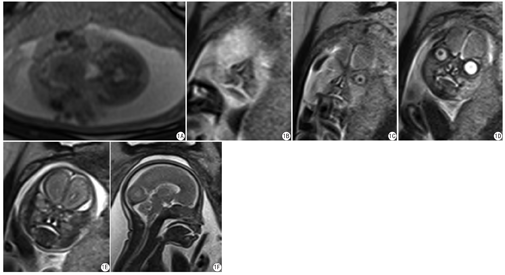

各层面评分结果详见表2。扫描失败的层面:HASTE序列中六6个扫描平面关键层面缺失,其中包括1个横断面、2个冠状面和3个矢状面;6个扫描平面存在运动伪影导致扫描失败,其中包括3个横断面、1个冠状面和1和矢状面。TRUE-FISP序列中12个扫描平面关键层面缺失。其中包括1个横断面、4个冠状面和7个矢状面;1个扫描平面(横断面)存在运动伪影导致扫描失败。两个序列扫描成功的层面进行相互补充评价后,横矢冠三个层面均扫描成功的有15例(75%),两个层面扫描成功的有5例(25%)。两个序列联合运用可以更全面显示唇和腭的结构(图1)。

横断面的扫描中,TRUE-FISP序列优于HASTE序列,矢状面的扫描中,TRUE-FISP序列劣于HASTE序列。在冠状面的检查中,两个序列的扫描成功率区别不明显。冠状面在评价唇裂时常能提供较为确切的证据,故两个序列在评价唇裂时的诊断效能差别不大。横断位对于上颌骨及牙蕾的连续性观察尤为关键,即评价唇裂是否合并槽突裂或腭裂时作用较大。矢状位在观察软腭裂时有辅助作用,但不及横断位敏感,故在评价腭裂时,HASTE序列的敏感性、特异性和准确性均低于TRUE-FISP序列。

从序列特征角度分析,HASTE序列拥有更高的空间分辩率,同时也拥有更长的扫描时间,对运动更加敏感。TRUE-FISP序列相对HASTE序列来说,空间分辨率较低,但拥有更小的反转角、更快的扫描时间,时间分辨率更高,更不易受到运动伪影的影响,层间距和层厚的修改不会影响图像质量,可以做薄层负间隔扫描,增加关键层面获取的几率,有助于唇裂合并腭裂的诊断,但由于其空间分辨率低,在矢状位观察结构精细的软腭时不如HASTE序列,不适合用于精确地评价软腭裂的程度。